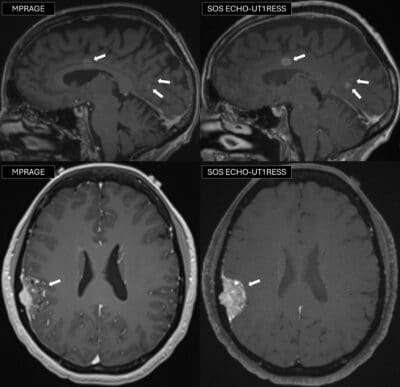

Innovatív MRI-technika lehetőségei az agydaganatok pontosabb kimutatásában

Az agydaganatok pontos kimutatásában a kontrasztanyagos mágneses rezonancia vizsgálat (MRI) kiemelt szerepet játszik. A klinikai gyakorlatban leggyakrabban alkalmazott MPRAGE szekvencia jól ábrázolja a daganatokat, ugyanakkor bizonyos esetekben – például apró áttétek felismerésénél – lehetnek korlátai.

Kutatásunkban egy kísérleti módszert, a SOS echo-uT1RESS szekvenciát vizsgáltuk, és hasonlítottuk össze a klinikai gyakorlatban használt hagyományos eljárással. Eredményeink szerint az új technika közel kétszeres javulást biztosít a daganat és az egészséges agyszövet elkülönítésében, ami különösen a kisméretű elváltozások jobb láthatóságát eredményezte. Fontos, hogy mindez a képminőség romlása nélkül valósult meg, ami arra utal, hogy a SOS echo-uT1RESS ígéretes eszköz lehet az agydaganatok korszerű és pontosabb diagnosztikájában. A vizsgálat két Egyesült Államok-beli centrum közös kutatásaként valósult meg, a National Institutes of Health (NIH) támogatásával – írta összefoglalójában dr. Tóth Adrienn és dr. Varga-Szemes Ákos.

3 Tesla stack-of-stars echo unbalanced T1 relaxation-enhanced steady-state MRI for brain tumor imaging: post-contrast comparison with MPRAGE

Cancer Imaging volume 25, Article number: 101 (2025).

https://doi.org/10.1186/s40644-025-00924-7